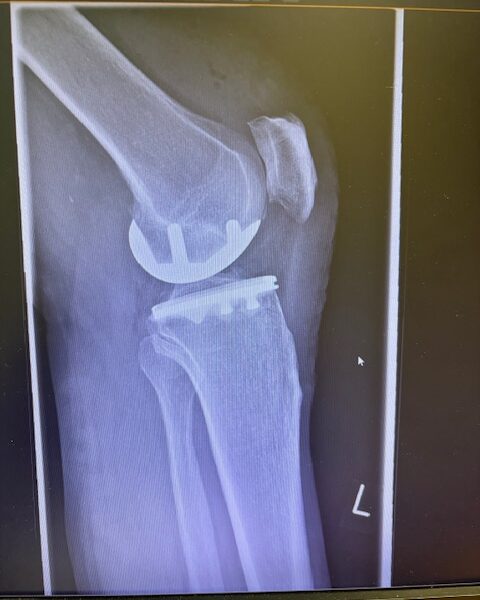

Ο ακτινολογικός έλεγχος (ακτινογραφίες/μαγνητική τομογραφία) ανέδειξε προχωρημένη οστεοαρθρίτιδα του έσω κονδύλου, με πλήρη διατήρηση του έξω διαμερίσματος και της επιγονατιδομηριαίας άρθρωσης. Με βάση αυτά τα ευρήματα, ο ασθενής ήταν ιδανικός υποψήφιος για μερική (μονοκονδυλική) αρθροπλαστική γόνατος.

Η επέμβαση πραγματοποιήθηκε με ελάχιστα επεμβατική προσπέλαση και τοποθέτηση πρόθεσης μόνο στον έσω μηροκνημιαίο διαμέρισμα του γόνατος.

Η ακριβής προσαρμογή του εμφυτεύματος επιβεβαιώθηκε διεγχειρητικά, εξασφαλίζοντας σταθερότητα και φυσική κίνηση της άρθρωσης.

Στον ασθενή τα εμφυτεύματα που χρησιμοποιήθηκαν είναι της εταιρείας Zimmer-Biomet Persona Μηριαίο μέγεθος 6, κνημιαίο μέγεθος Η και ενθέμα (inlay) Η li. 8mm.